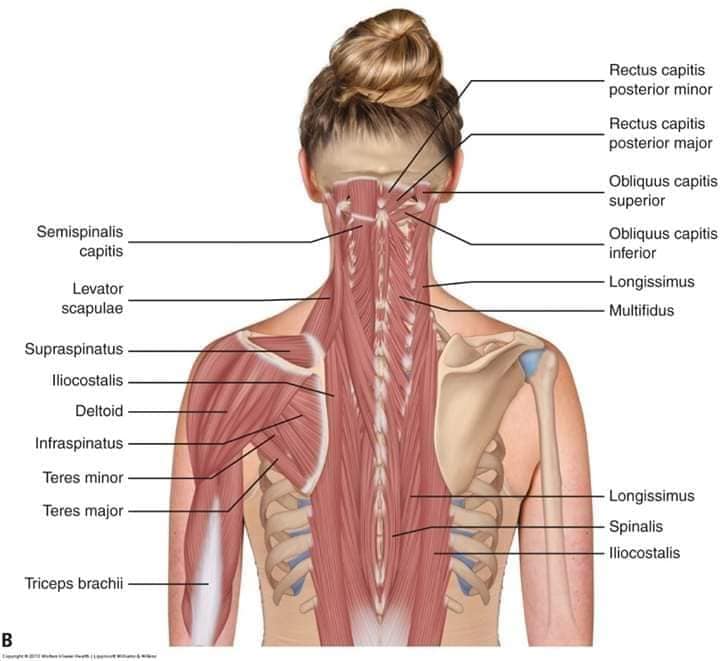

Спинні м'язи

Спинні м'язи виконують функції підтримки хребта, а також дозволяють здійснювати рухи тулуба.

Поверхневі спинні м'язи

М'язи, що піднімають лопатку: Трапецієподібний м'яз: великий м'яз, що покриває верхню частину спини. Його функція - підтримка і рух лопаток, а також забезпечення стабільності хребта.

М'язи, що ведуть лопатку до хребта: Широкий м'яз спини: великий м'яз, що розташований в нижній частині спини. Він відповідає за рухи плечей і лопаток, а також за розширення верхньої частини тулуба.

Глибинні спинні м'язи

М'язи, що забезпечують стабільність хребта: М'язи, що розташовані між хребцями: включають мускулатуру, яка забезпечує стабільність і підтримку хребта, а також дозволяє здійснювати рухи хребта.

М'язи, що здійснюють ротацію та нахили

М'язи, що забезпечують ротацію хребта: Ротаційні м'язи: допомагають у здійсненні обертальних рухів тулуба, а також у підтримці рівноваги і стабільності хребта.